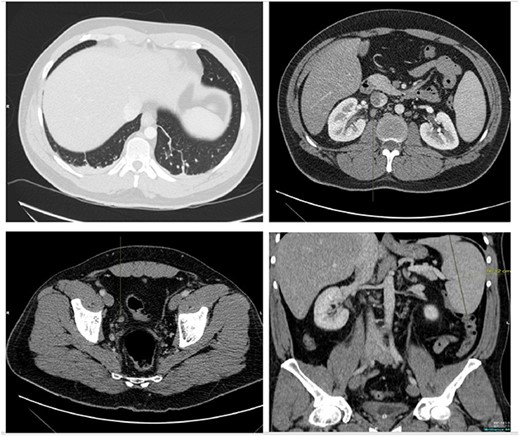

He presented with right sided abdominal pain associated with jaundice, fever, myalgia and arthralgia after receiving his second dose of the penultimate cycle of intra-renal BCG instillation. He did not have any tuberculosis contacts. His parameters on admission were stable. C-reactive protein levels were 230 mg/l and white cell count (WCC) was 6.51 × 109/l. His liver function tests were deranged, with a mixed obstructive and hepatitic picture. A CT kidneys, ureters and bladder (KUB) showed mild diffuse dilatation of the right ureter and renal pelvis with minimal amount of peri-ureteric fat stranding (Fig. 1). A CT scan of the abdomen with intravenous contrast (IV) was performed, this showed a distended right ureter down to the vesicoureteric junction, peri-ureteric fat stranding and lymphadenopathy in the aorto-caval space together with splenomegaly and atelectatic changes (Fig. 2).

An initial CT KUB showed mild diffuse dilatation of the right renal pelvis (as indicated by the arrow).

A CT scan of the abdomen with IV contrast showed atelactic changes in the lung bases (top left), reactive hilar nodes (top right), a distended right ureter all the way down to the vesicoureteric junction surrounded by fat stranding (bottom left) and splenomegaly (bottom right).